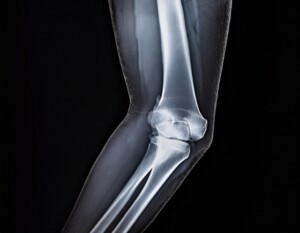

レントゲンでは見えない膝痛

「軟骨がすり減っている」

「年齢だから仕方ない」